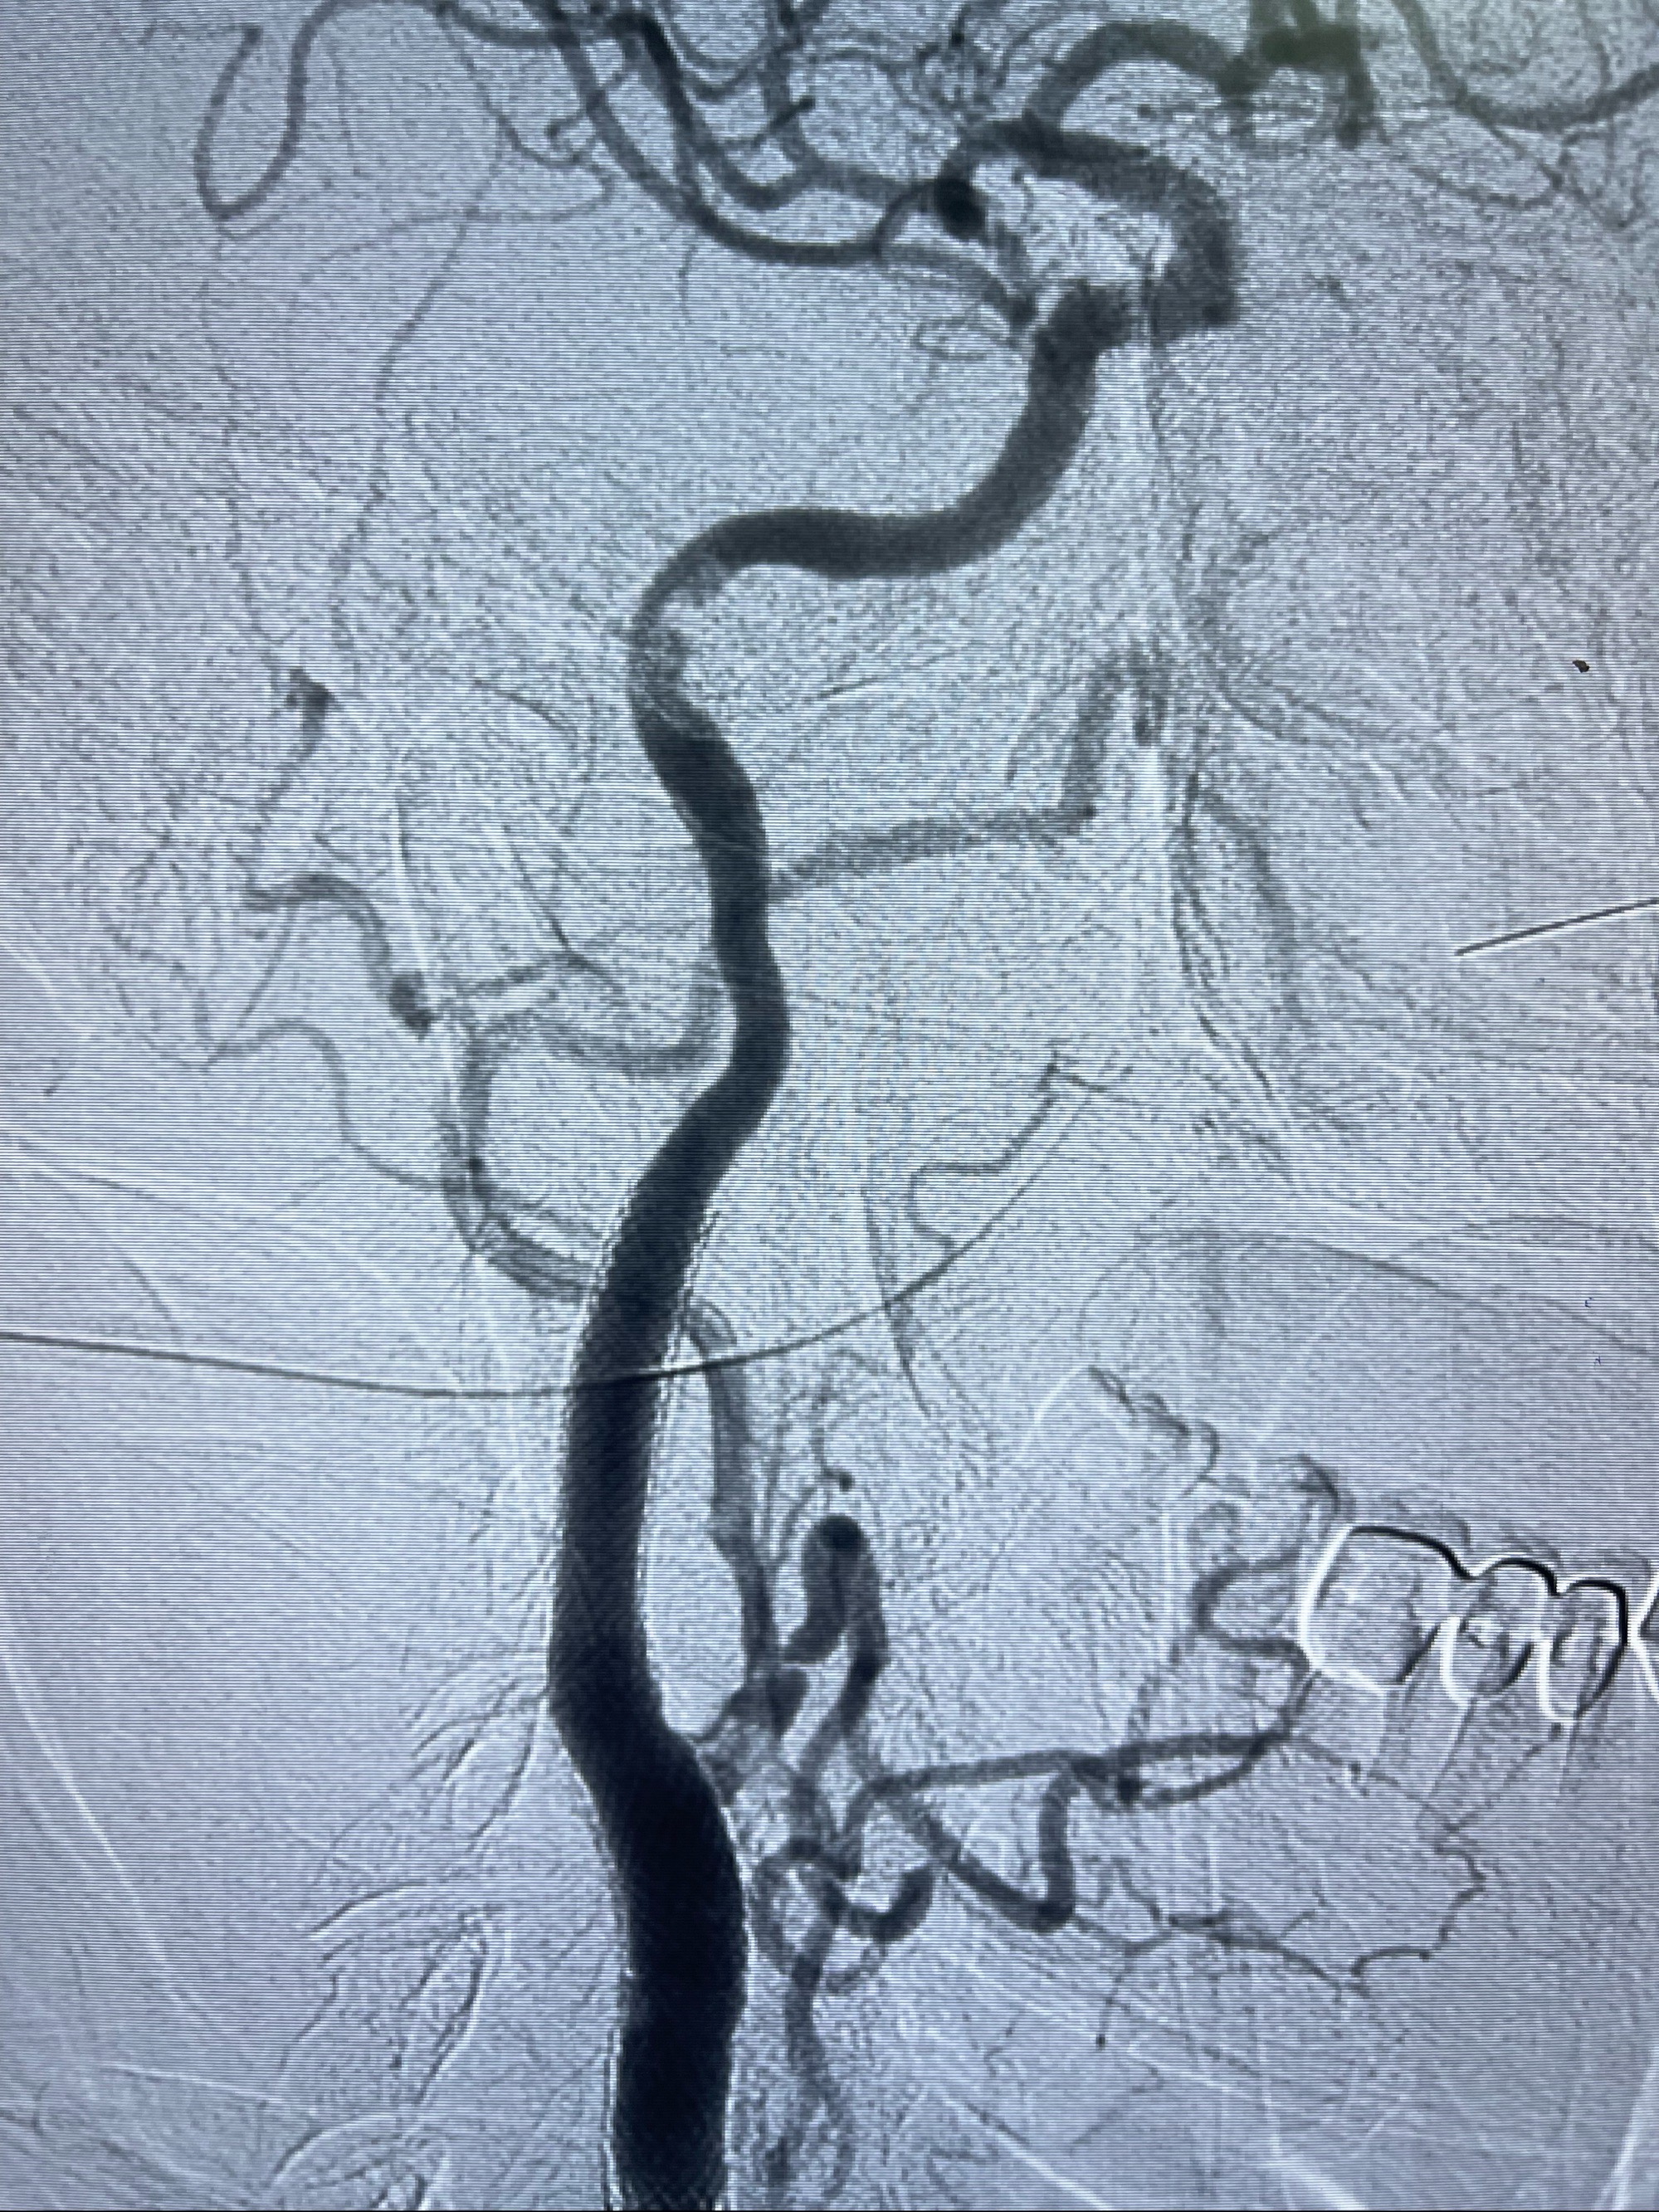

2023-07-10DSA:右侧颈内动脉岩骨段夹层伴中偏重度狭窄改变,左侧颈总动脉闭塞、右侧颈外动脉由右侧肋颈干甲颈干吻合代偿

箭头所示为颈内动脉岩骨段重度狭窄,结合MRI,考虑为肿瘤侵犯右侧颈内动脉

箭头以近至支架段管腔不规则狭窄